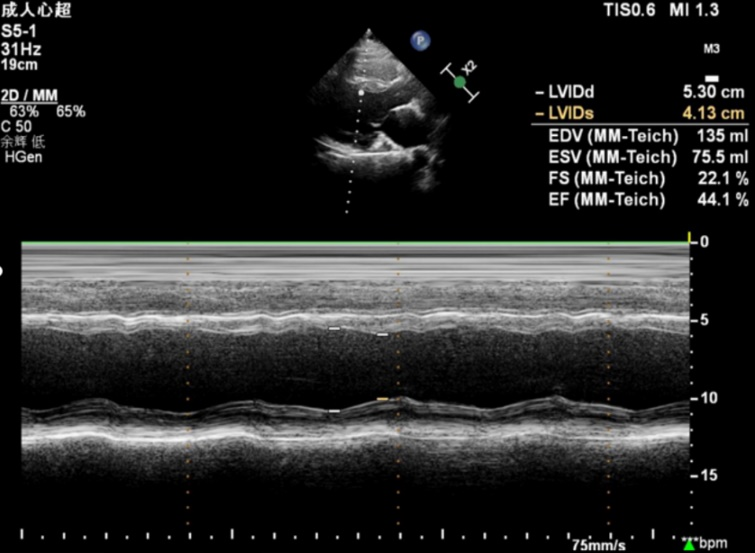

17岁的小敖胸闷、憋气已有2年,近5个月来症状加重,在当地医院进行心脏超声检查发现左心室射血分数(LVEF)降低,为寻求进一步治疗来到青大附院市南院区心血管内科门诊。辛辉主任、高娟主治医师进行详细检查后发现,患者LVEF为44%,且伴有左心扩大、左心室壁炎性表现、左心室收缩运动异常、左心室心肌过度小梁化等,初步诊断为慢性心力衰竭急性发作、炎性心肌病。在进一步询问病史后,治疗团队了解到患者舅舅患有全身肌肉萎缩、瘫痪,两名表弟患有轻度肌肉萎缩,这引起了团队的警觉,立即组织放射科、神经内科、风湿免疫科、心脏超声科、肾病科等多学科专家进行疑难病例讨论。

多学科专家团队结合病情,根据相关指南及专家共识诊疗路径,为患者进行了全面检查,发现患者双上肢肌力为4级、双下肢肌力为4级,且腓肠肌肥大,走路呈鸭步步态,抗SM抗体、抗核糖核酸蛋白抗体为强阳性,尿液葡萄糖、红细胞、蛋白为阳性,初步考虑患者为肌营养不良引起的慢性心力衰竭急性发作。在进一步进行基因检测后,最终确诊患者为贝氏肌营养不良性心肌病,并在神经内科副主任王海萍教授的协助下,成功实施精准治疗。